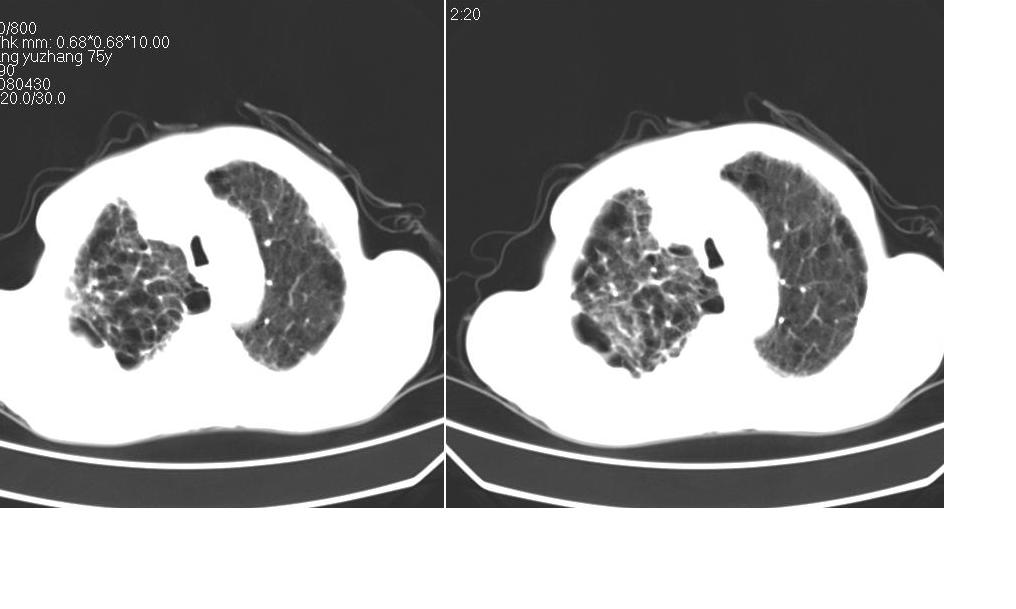

以下是引用zsl6918在2008-5-3 19:53:00的发言:[br]右肺中心型肺癌并纵隔淋巴结转移,胸膜转移,右肺癌性淋巴管炎。

以下是引用liuyue在2008-5-3 20:49:00的发言:[br]1.右侧中心型肺癌伴双肺转移瘤、纵隔淋巴结转移、右侧胸腔积液(侵及胸膜所致可能性大)。[br]2.右肺阻塞性肺炎,癌性淋巴管炎不除外。

以下是引用mzh123在2008-5-3 21:12:00的发言:[br]本人持有不同观点[br]1、右肺似有团块表现,但只有一个层面,所以本人认为还是以片为主,所以不能首先考虑肿瘤[br]2、右肺普遍成纤维化改变 并伴有片状炎症改变,和癌性淋巴管炎表现不同[br]3、所以本人认为是间质纤维化伴感染可能大 及胸腔积液